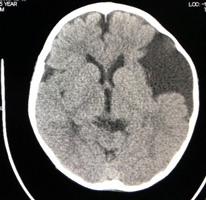

水頭症

水頭症とは病態を総称したものであり、小児脳神経外科領域で対応する水頭症は図(胎児水頭症ガイドラインより)の通りさまざまな原因によって発症します。そのために発症による日常生活動作の状態もさまざまです。

2つの画像のキャプション:胎児水頭症診断と治療ガイドライン(2010)より抜粋

水頭症はどのような状態であっても発症しているこどもの発達の足かせとなるため、治療が必要です。現在水頭症の治療には2つの方法があります。ひとつは「シャント術」と言われる短絡術、もうひとつは神経内視鏡を用いた「第三脳室底開窓術」です。